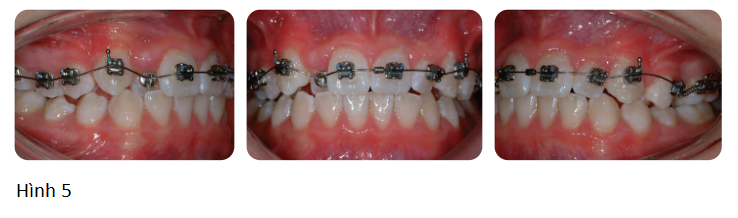

Bác sĩ sử dụng khí cụ nong nhanh hàm trên gắn với ốc HYRAX để gắn vào hàm trên và yêu cầu bệnh nhân kích hoạt ốc mỗi ngày 1 lần trong vòng 10 ngày liên tiếp. Sau đó, gắn headgear kéo trước và tác động một lực phía trước vào xương hàm trên thông qua thun kéo liên hàm giữa các hook gắn trên khí cụ và facemask của headgear kéo ra trước. Lực tăng dần trong 8 tuần để tới 400g hai bên và vị trí của thanh trên facemask được điều chỉnh sao cho lực song song với mặt phẳng cắn, giới hạn tác dụng xoay trên hàm trên. Bệnh nhân được khuyến cáo đeo facemask ít nhất 16 tiếng mỗi ngày.

Headgear kéo trước thường sử dụng cùng với khí cụ nong nhanh hàm trên bởi vì nhiều trường hợp sai khớp cắn hạng II có xương hàm trên cũng bị hẹp theo chiều ngang, dẫn đến chen chúc và cắn chéo răng sau. Theo lý thuyết, việc kết hợp sử dụng khí cụ nong hàm nhanh cũng làm lỏng hoặc tách khớp quanh xương hàm trên, làm di chuyển tổ hợp hàm trên xuống dưới và ra trước dưới lực của headgear.